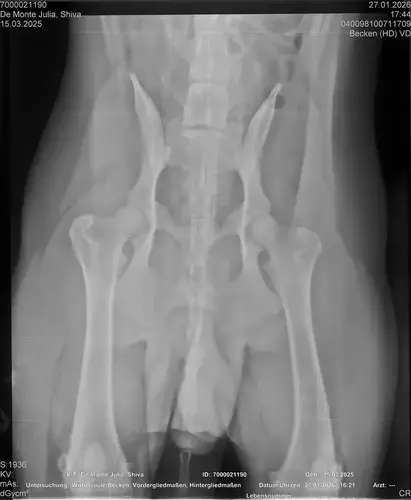

Vorige Woche kam mir Shiva verändert vor, nicht der aufgeweckte Spaßvogel der er sonst ist. Ich dacht vl ist er im Garten iwie blöd ausgerutscht weil unser gesamtes Grundstück über Wochen von einer dicken Eisschicht überzogen war. Er lag viel rum, zuviel da er doch zu den Wirbelwinden unter den Junghunden gehört. Er quetschte sich zum schlafen an mich ran, was auch untypisch für ihn ist. Er ist immer so „iiiii fass mich nicht an“. Ich nehms ihn nicht böse er ist nicht der große Kuschler :D Hat er wohl von mir :D :D aber er pickte nur an mir dran, ruhen ohne Körperkontakt war nicht möglich. Fand ich schön aber da ich wusste dass es nicht Shiva ist machte ich mir schon Sorgen… Am nächsten Tag wollte ich ihn bürsten alles war wie immer, er legte sich hin und sah mir zu wie ich einen Fellberg stapelte. Bei seinen Hinterpfoten hörte ich auf und dachte mir ich fühl mal vorsichtig.. Plötzlich knurrte er mich an vor Schreck weil ich damit überhaupt nicht gerechnet hatte zuckte ich reflexartig zurück (was lt Trainerin ein Fehler war)… Aber ich hab nicht mit einer derartigen Reaktion gerechnet, Shiva hatte schon 2 kleine Verletzungen die ich ohne Probleme verarzten konnte. Am nächsten Tag gings ab zum TA. Mit Maulkorb da ich nichts riskieren wollte. Nach der Untersuchung wo er auch mehrmals knurrte gings ab zum röntgen. Und das riss mir den Boden unter den Füßen weg. Dann die Aussage von der TA „ich weiß sie wollen einen gesunden jungen Hund aber das ist Shiva leider nicht“. Was jetzt? Er ist so ein aufgewecktes Kerlchen, absolute Lieblingsbeschäftigung ist Parcour. Er macht es so gern, ja auch UO und Suchspiele aber das leuchten in seinen Augen wenn wir Geräte machen :( (er macht noch keine schweren Geräte wie A Tafeln oder springen… Aber die seichten macht er mit absoluter Leidenschaft.. Ruhe halten über mehrere Monate… nur langsames gehen oder schnüffeln.. puh ich weiß nicht wie ich ihm verbieten soll zu rennen und zu toben… Vl habt ihr Tipps für mich. Im Anhang der Befund und ein paar Bilder vom kleinen Wirbelwind. <3

Ich lese da draus, dass der Hund in mindestens einem Ellenbogen nicht sauber ist, HD "noch zugelassen" oder "mittel" hat, nen' 1er LÜW UND vielleicht sogar OCD. Das wär ja wahnsinnig...

• Naja die Diagnose kommt von einem „Facharzt“, lt TA war ihrerseits alles i.O. Sie wollte noch sicher gehen und die Bilder zur weiteren Befundung einschicken und das kam dabei raus. Und der Therapievorschlag beläuft sich auf Ruhe, Ruhe und noch mehr Ruhe. Und einer Schmertherapie von Gabapentin 800mg 1/2 Tablette 2x tgl, Carprodyl 120mg 1 1/2 Tabletten 1x tgl und TamaCan CBD Tropfen 10-15 Tropfen 2x tgl. 1x in der Woche soll ich telefonisch Auskunft geben wie es Shiva geht. Das ganze mal für 14 Tage. Sie meinte noch sie hat viele Junghunde die ein Leben lang Schmerzmittel nehmem müssten. Die Röhrenknochenentzündung heilt in der Regel von selber der Rest gehört beobachtet… Ich weiß im Moment auch nocht so recht.. Er tut mir nur wahnsinnig leid mit sovielen Diagnosen und für mich war erstmal vorrangig ihn schmerzfrei zu bekommen. Das ist er inzwischen und versteht die Welt nicht mehr warum er nicht wie sonst spielen und arbeiten darf. Im Anhang noch Röntgenbilder falls sich jemand damit auskennt bzw Interesse hat..

• Ok, die Röntgenbilder sind aber auch extrem schlecht.

Wenn dieser Panostitis-schub rum ist, würde ich dem Rest nochmal nachgehen. Man kann bei Dr. Tellhelm ( SV Gutachter) ein privatgutachten in Auftrag geben, das kostet um die 100€. Da kriegst du halt ne konkrete Einstufung und nicht "verdacht auf" und "könnte hiermit ODER damit in Verbindung stehen", etc.

Ich denke aber, dass du für ein Gutachten von Tellhelm nochmal neu röntgen lassen musst, ich finde, dass das Bild der Hüfte (HD und LÜW wird da beurteilt) und die Draufsicht auf die Ellenbogen (nötig zur Beurteilung von ED) unterirdisch sind!